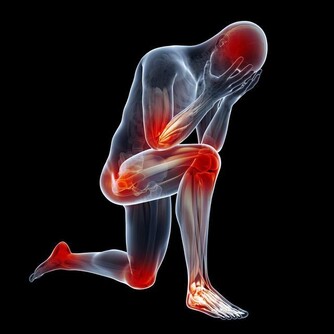

如果我們吃下去,很可能會出現急性中毒,發燒、腹痛、嘔吐、厭食等身體上的不適至少得折磨我們三五天,